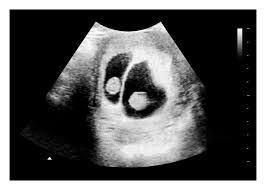

What are the chances of having twins? When six full weeks have passed (after week 6+0) you should be able to detect all kinds of twins using ultrasound. A full bladder provides an ultrasonic window to better see what's inside the uterus. I've been posting in october 2012 since i found out i was pregnant in february. 6 weeks 4 days pregnant progress check in the 7th week of pregnancy, your baby's lungs are starting to develop. They confirmed the presence of a gestational sac, yolk sac and fetal dipole, but could not detect a heartbeat. Between 5 ½ to 6 ½ weeks, a fetal pole or even a fetal heartbeat may be detected by vaginal ultrasound. The fetal pole is the first visible sign of a developing embryo.

The exact time twins can be detected depends on the type of twins, for example, if they're identical (from one egg) or not. By eight weeks of your twin pregnancy, your babies will have buds for limbs that look like little paddles. Mehr als 200.000 maschinen sofort verfügbar. Most doctors will schedule an ultrasound somewhere between 6 and 10 weeks of pregnancy to confirm the pregnancy and check for multiples. Six full weeks is when you're 6+0 weeks pregnant. I should be 7 weeks, 4 days according to last period. (florida) i suspected i had twins because my beta numbers were high, i had two big follicles during my iui and i'm already big for less than 7 weeks! Seeing twins at 6 weeks is definitely possible. Besides ultrasound at 4 weeks, there are several changes during pregnancy for moms to expect. By four weeks, twins will start showing during ultrasound in form of 2 gestational sacs, but you cannot get clear indication of twins until 6 weeks. The first time i spotted but the other two were gushes. This was taken at 4 weeks 6 days. Some women would rather not know until both twins are relatively safe, while others want to know even if the chances of losing one twin are high.

Between 5 ½ to 6 ½ weeks, a fetal pole or even a fetal heartbeat may be detected by vaginal ultrasound. In this 7th week of pregnancy, your baby's lungs are starting to develop. The ultrasound picture above is of identical twins who share a placenta at 6+2 weeks. Beauty points sammeln & mit der douglas beauty card von exklusiven vorteilen profitieren. This begins with a small lung bud branching out from the upper part of the tube (esophagus) between your baby's mouth. Get to know what you need to take care of when 4 weeks and 6 days pregnant pregnant. I've been posting in october 2012 since i found out i was pregnant in february. You have approximately a 3.35 chance of having twins naturally , without the help of any fertility treatments. They said the baby looked small and measured about 6 weeks. 4 weeks) between 5 ½ to 6 ½ weeks, a fetal pole or even a fetal heartbeat may be detected by vaginal ultrasound. Little arms and legs sprout. You don't hear heartbeats any earlier or later with twins, that i know of. Mehr als 200.000 maschinen sofort verfügbar.